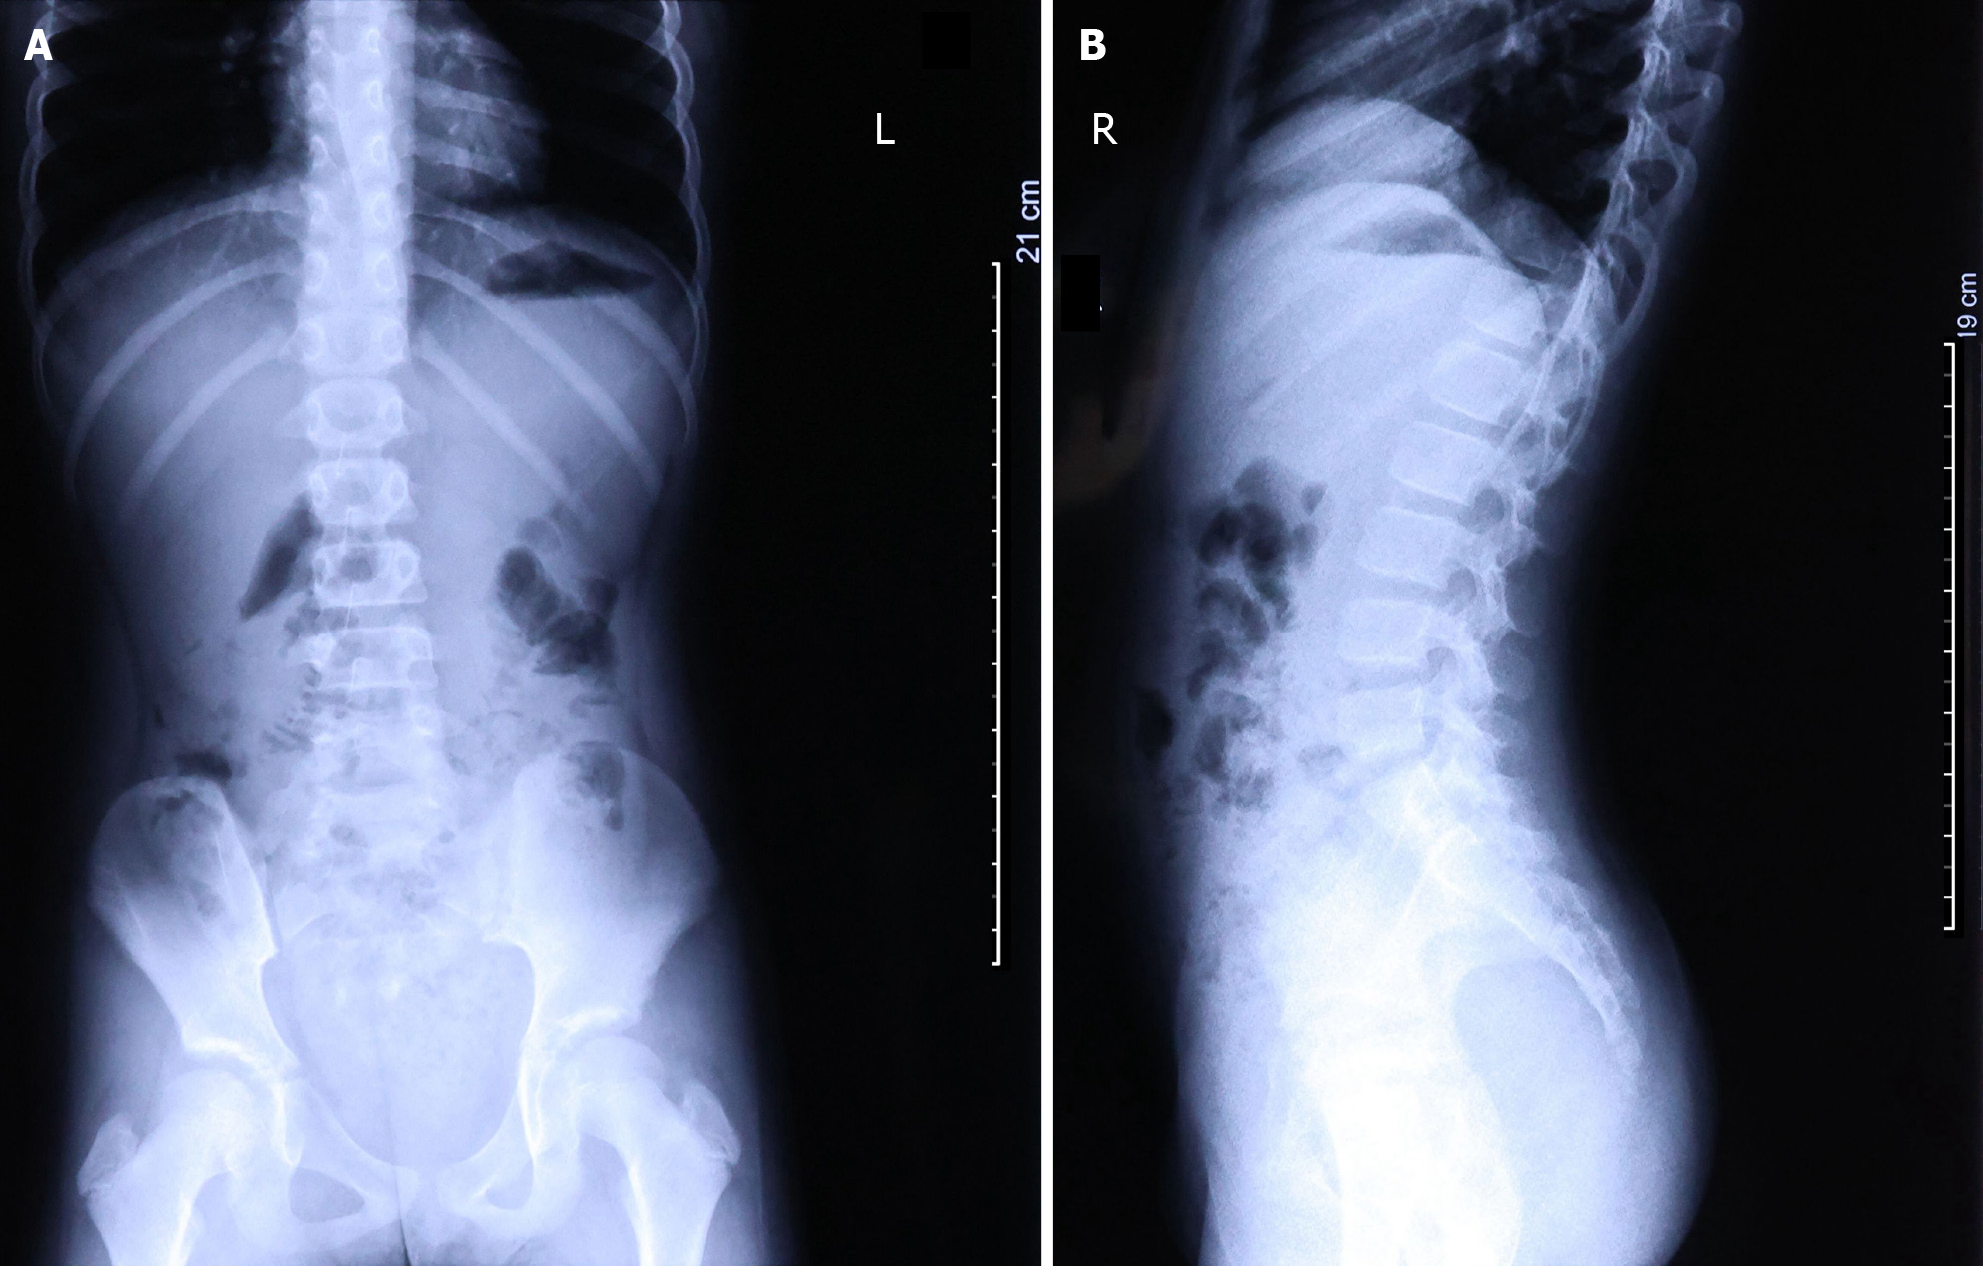

Following the physical examination, the child underwent an abdominal ultrasound, digestive system X-ray, and blood test. Abdominal ultrasound findings revealed abnormally dilated loops of the jejunum and ileum in the left and lower left abdomen, containing a large amount of chyme under high tension. The diameter of the intestinal tract was 3.1 cm. A substantial number of cord-like hypoechoic areas were visible between the intestines; a significant amount of ascites, with a depth of approximately 2.8 cm and turbid sound transmission, was present in the abdominal cavity. The mesentery was notably swollen; the ileocecal region was slightly swollen, and the wall of the terminal ileum was thickened, measuring approximately 0.6 cm. Radiographic examination revealed poor aeration of the small intestine in the lower abdomen along with the presence of air-fluid levels (Figure 1).